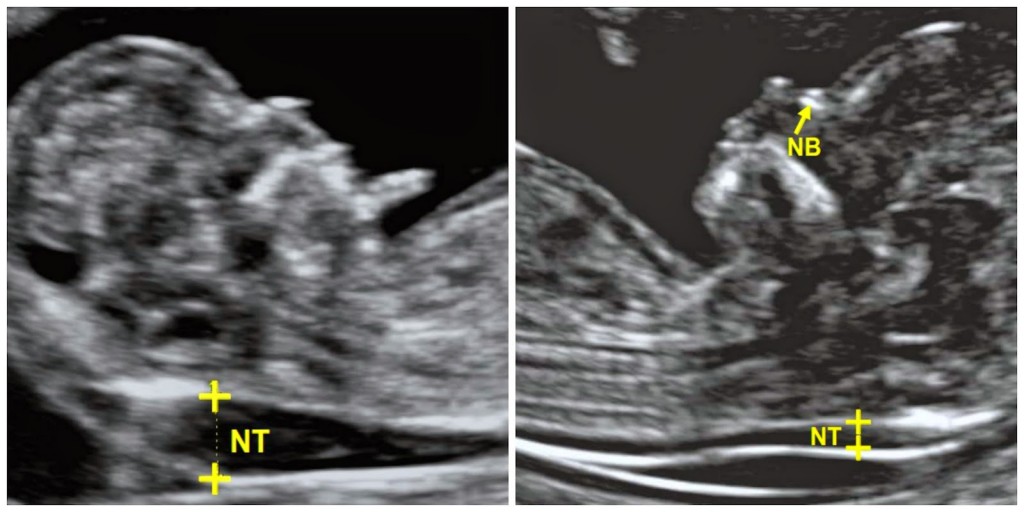

La translucencia nucal es una acumulación de líquido debajo de la piel en la parte posterior del cuello del feto.

Todos los bebés tienen un poco de líquido en la zona de la nuca, pero en bebés con síndrome de Down la cantidad de líquido es mayor, y por tanto las medidas son mayores.

| Imagen izda. NT. pliegue nucal aumentado. Imagen dcha. NT pliegue nucal normal |

Suele ser recomendable acudir al examen para la exploración nucal con la vejiga llena, ya que así la vejiga empuja el útero y permite obtener una visión más clara. Es una prueba indolora, aunque se puede sentir algo de presión en el abdomen.La medida del pliegue nucal puede detectar alrededor del 77% de los bebés con síndrome de Down. La prueba de translucencia nucal sólo puede estimar el riesgo de que su bebé tenga síndrome de Down. No es fiable al 100%. El riesgo se expresa como un porcentaje, así si el resultado es 1 en 1000, significa que de cada 1.000 bebés con ese nivel de riesgo, 1 tendrá síndrome de Down. Un riesgo de 1 en 150 o menos se considera un riesgo alto. En esta prueba pueden producirse falsos positivos cuando los resultados pueden sugerir que un bebé tiene un alto riesgo de tener síndrome de Down, a pesar de que el riesgo es realmente bajo. La tasa de falsos positivos para en este tipo de pruebas es del 5%. Por eso la medida del pliegue nucal se combinan, junto con los resultados de un análisis de sangre, en el que se miden los niveles de la hormona hCG beta y de la proteína PAPP-A. En los bebés con síndrome de Down, los niveles de la hormona hCG beta son altos y los de la proteína PAPP-A son bajos. Para valorar el riesgo también se tiene en cuenta otros factores como la edad de la madre Cuando la medida del pliegue nucal se combina con los resultados del análisis de sangre, la tasa de detección aumenta a 90%. La tasa de falsos positivos de la prueba combinada es también un 5%.